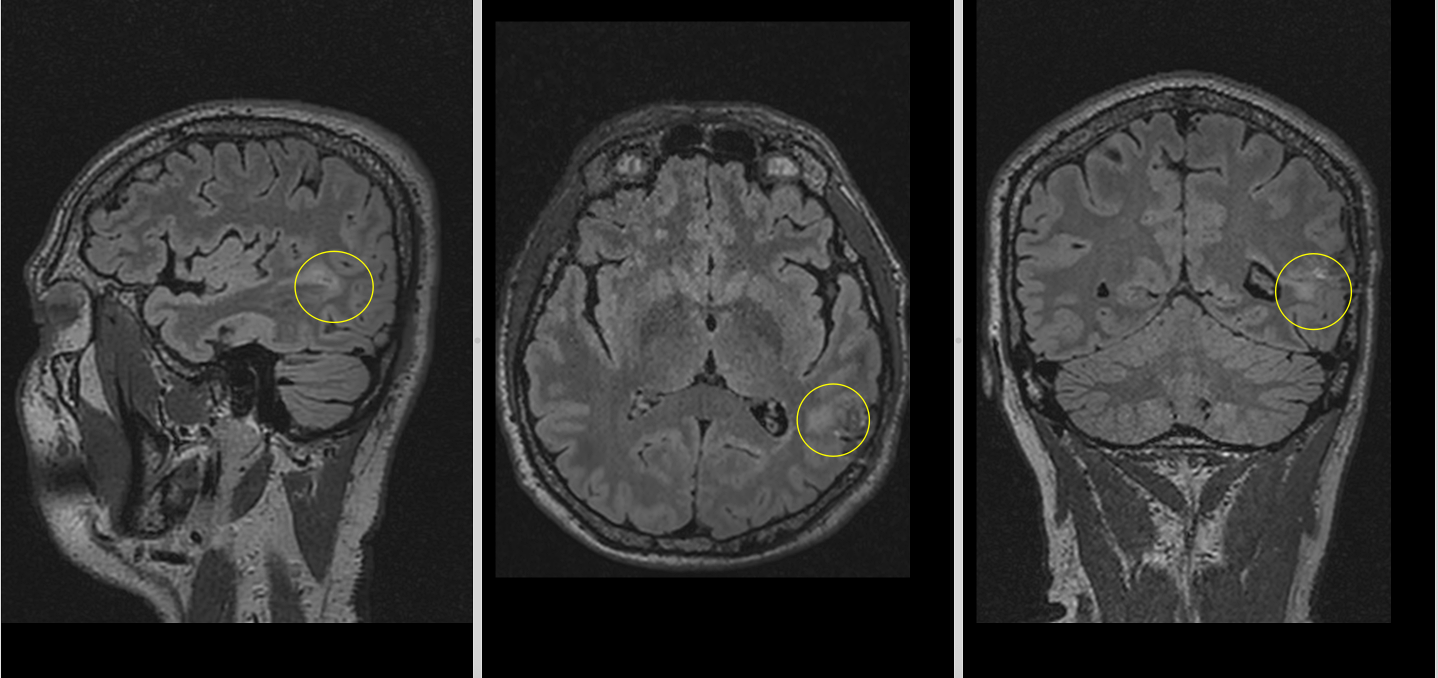

Postoperator, evoluția imediată a fost foarte bună. Pacientul a avut o stare generală și neurologică excelentă, fără niciun deficit nou, iar CT-ul cerebral de control nu a evidențiat complicații locale, precum hematom sau alte colecții postoperatorii. RMN-ul cerebral efectuat ulterior a arătat că a rămas un rest tumoral în substanța albă profundă a emisferului stâng. Acest aspect este important și trebuie explicat clar pacienților: în chirurgia glioamelor infiltrative din ariile elocvente, uneori nu cea mai agresivă rezecție este cea mai bună opțiune, ci cea care păstrează echilibrul între controlul oncologic și păstrarea funcției neurologice.

La 1 an după operație, controlul imagistic a arătat o reducere semnificativă a restului tumoral de la nivelul pereților cavității de rezecție, acesta devenind aproape imperceptibil pe unele secvențe. Clinic, pacientul avea o viață normală, fără deficite neurologice și fără crize epileptice.